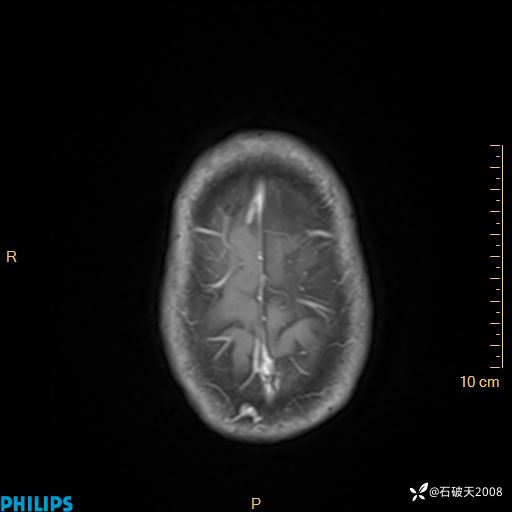

2024.2.21MR

DWI

ADC